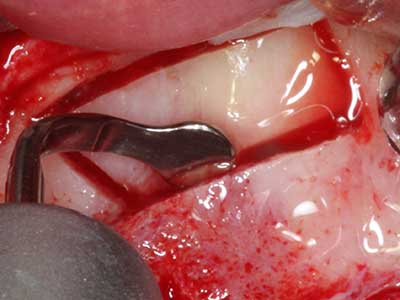

Quando le procedure chirurgiche vengono eseguite sull'osso nelle immediate vicinanze di strutture sensibili, come vasi sanguigni o nervi, gli strumenti rotanti pongono un rischio significativo di lesione iatrogena. I dispositivi piezoelettrici possono essere utili per la preparazione delle coperture ossee e la rimozione del tessuto duro in prossimità dei nervi, in particolare per la loro esposizione dopo una lesione iatrogena, ma anche durante la lateralizzazione dei nervi per le procedure di resezione e ricostruzione o il posizionamento di impianti (figg. 17-20). Il contatto leggero tra puntina piezoelettrica e nervo non causa generalmente danni, ma se si procede senza prestare attenzione con movimenti a sega o raccordi con residui di substrati ossei possono verificarsi danni al nervo temporanei o anche permanenti. Il rischio di danno, tuttavia, è considerato sostanzialmente inferiore al rischio presente utilizzando seghe o frese (Pereira, Gealh et al. 2014).